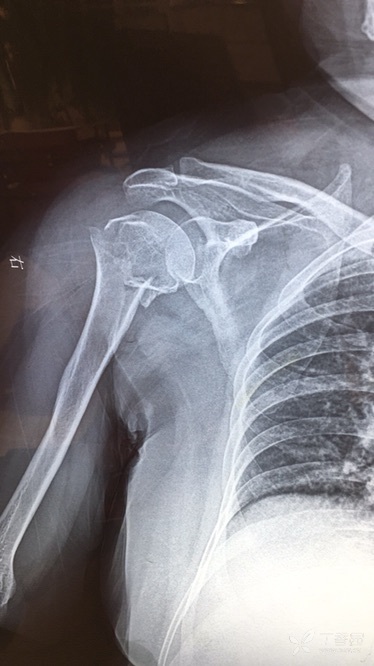

摘要:最新骨颈骨折信息分享,不要慌张。鼓励患者积极面对,因为骨颈骨折可治愈。提醒患者不要错过探索大自然的美景,生活中的美好等待你去发现。这是一个关于骨颈骨折的积极态度和鼓励面对挑战的简短摘要。

当我们谈论“骨颈骨折”,许多人可能会感到恐惧和困扰,但今天,我想邀请你们换一种视角看待这个问题,让我们以最积极、最乐观的心态,一起去迎接一次与大自然的亲密接触,骨颈骨折并不意味着生活的终结,相反,它是我们重新审视生命、寻找内心平静的一个契机。

骨颈骨折只是生活的一个小挑战,它不应该成为你探索世界的绊脚石,相反,它应该成为你重新认识生命、发现自然美景的契机,当你重新站起来,你会发现自己的内心变得更加坚韧和勇敢。